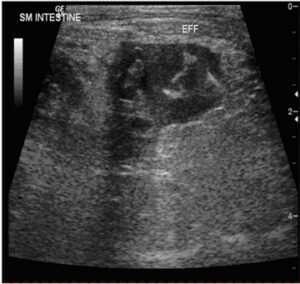

| Figure 2: Small volume of a cellular effusion (ingesta) next to the small intestine in a dog. The dog had been bitten by another dog, rupturing the bowel. |